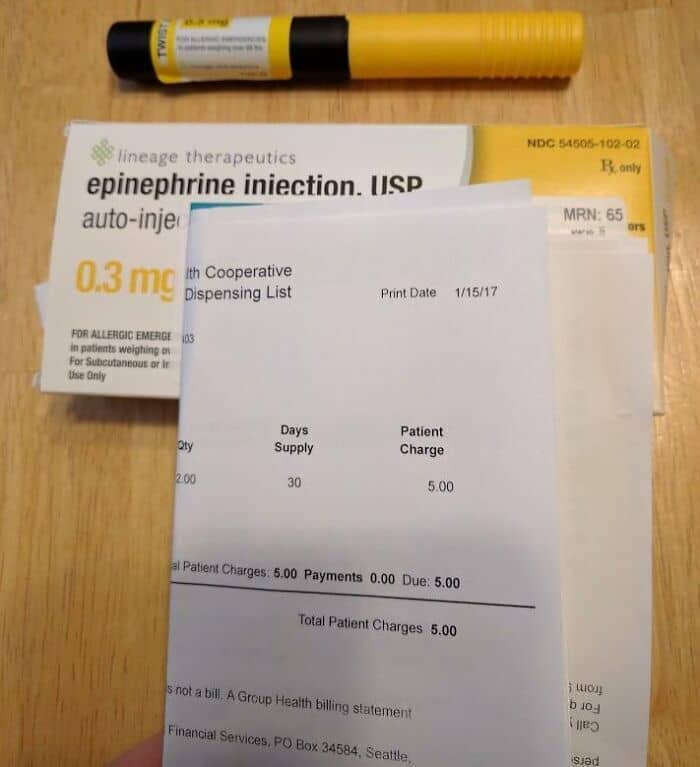

#91 $5 For Two Generic Epipens! In The Past, My Insurance Company Didn’t Give Me A Choice And I Had To Always Buy Name Brand